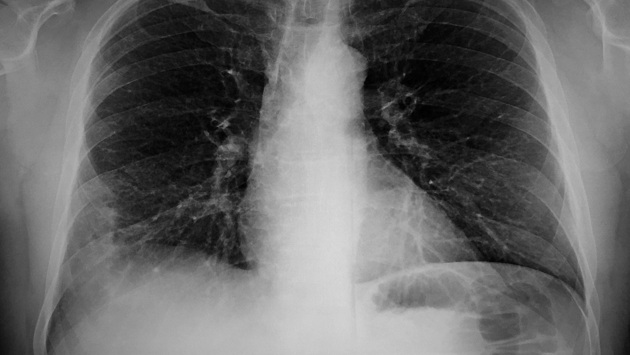

В разговоре с «Газетой.ру» Ким сообщила, что самые частые симптомы микоплазменной пневмонии – сухой кашель, лихорадка и першение в горле. Врач настояла, что при появлении этих симптомов нужно обращаться к врачу.

Заразиться микоплазменной пневмонией можно как воздушно-капельным путем, так и в случае активации вируса внутри организма. Такое происходит, если человек уже является носителем инфекции. Инфекция дает о себе знать после переохлаждения, в стрессовой для организма ситуации.

Если говорить о лече6нии микоплазменной пневмонии, в терапии применяются антибактериальные препараты, но их назначают после того, как будет определен возбудитель. Для этого берут на анализ мокроту, смывы, лаважную жидкость, соскоб эпителиальных клеток ротоглотки, слюну. Также определяют антитела Ig М, IgG и Ig А к Mycoplasma pneumoniae в крови.

Высокий риск заболевания микоплазменной пневмонией существует в осенне-зимний период. При этом болезнь может развиваться как самостоятельно, так и как осложнение после перенесенного гриппа и ОРВИ. «Чтобы не допустить осложненного течения, эти болезни необходимо лечить. Лечение может быть этиологическими, когда удалось установить возбудитель, и неспецифическим — это соблюдение постельного режима, обильное питье, витамины», – заключила Ким.